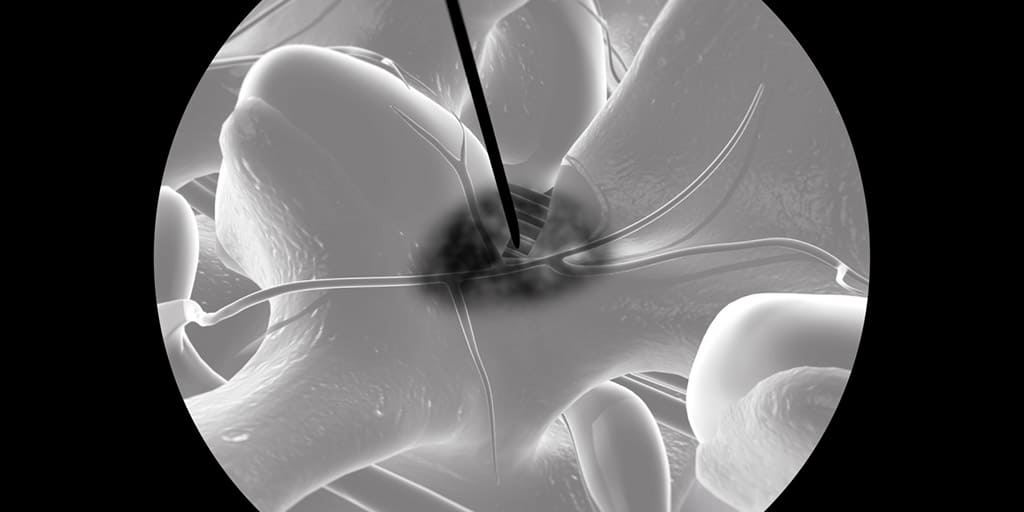

To Advanced Lumbar Bio-Skills Lab που έλαβε χώρα στις 12-13 Οκτωβρίου 2019 στο Άμστερνταμ της Ολλανδίας και διοργανώθηκε υπό την αιγίδα της Spine Intervention Society (SIS) έδωσε τη δυνατότητα στους συμμετέχοντες να διδαχθούν τις πιο προηγμένες και τεκμηριωμένες μικροεπεμβατικές τεχνικές στη σπονδυλική στήλη υπό την καθοδήγηση κορυφαίων εκπαιδευτών της SIS από την Ευρώπη και τις Ηνωμένες Πολιτείες Αμερικής και να εξασκηθούν σε ανατομικά παρασκευάσματα.